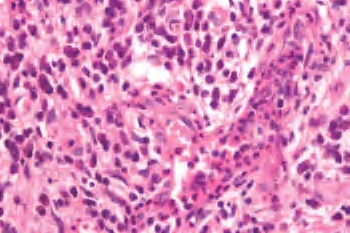

2.镜下 密布无干酪样坏死的小肉芽肿,背靠背排列,内含上皮样细胞、多核巨细胞。淋巴结结构部分或全部被破坏,淋巴结纤维化。随着病变发展,即使淋巴结全被肉芽肿取代,其轮廓仍保存而不融合。结节病具有愈合的倾向,肉芽肿可成为玻璃样变的硬化灶。也可见坏死,但只是一小部分的纤维素样坏死而不是干酪样坏死。

Schaumann小体最大径20~50μm,存在于巨细胞内或组织间隙,嗜苏木素着色,组织化学显示其中含铁或钙;星状体大小5~35μm,为蜘蛛状放射形结构,中央为2~4μm的核心,从此核心针状刺向周围放射。此两种小体是非诊断特异性的(图3-15至图3-17)。

图3-16 淋巴结结节病